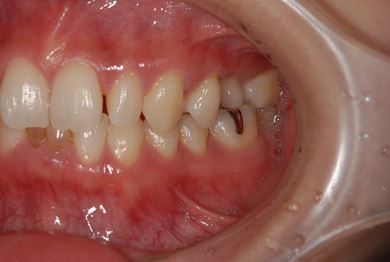

| 性別/年齢 | 女性 / 28歳 | ||||||||||||||||||||||||||||||||

| 主訴 | 下前歯の色が気になるので、ホワイトニングかセラミック治療できれいにしたい。(下前歯2本は乳歯でした) | ||||||||||||||||||||||||||||||||

| 治療方針 | 下顎前歯、乳歯を抜歯し、セラミック治療にて審美的回復を行う。 | ||||||||||||||||||||||||||||||||

| 治療内容 | エンプレスジルコニアフレームオールセラミッククラウンブリッジ4本 | ||||||||||||||||||||||||||||||||